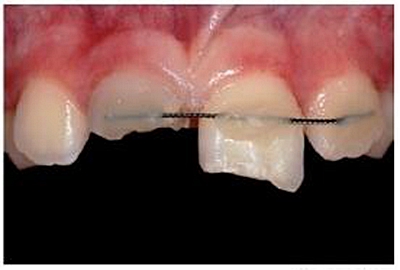

專業(yè)醫(yī)師對患者進(jìn)行了仔細(xì)檢查及診斷分析。11被診斷為冠根折伴牙髓暴露及大面積牙體缺損。21被診斷為側(cè)向移位伴冠折。檢查活動夾板在位,兩中切牙根管治療術(shù)中,氫氧化鈣根管內(nèi)封藥。11明顯變色。11用Cavit暫封,21復(fù)合樹脂充填。11腭側(cè)頸部有一折裂片。

牙本質(zhì)和牙釉質(zhì)經(jīng)過全酸蝕(酸蝕劑)后,涂布粘接劑(Syntac; Ivoclar Vivadent),準(zhǔn)備樹脂修復(fù)。利用已完成的硅膠導(dǎo)板輔助修復(fù)體的腭側(cè)成型(圖13)。牙本質(zhì)核采用不同顏色、不透光的牙本質(zhì)樹脂分層連續(xù)堆積

切端則采用透明樹脂,最后使用釉質(zhì)樹脂(Amaris, VOCO, Cuxhaven, Germany)。21的樹脂修復(fù)采用類似的方式。修復(fù)初步成型,拋光,恢復(fù)干燥牙釉質(zhì)的顏色。攝片顯示樁在根管內(nèi)位置合適(圖15)。最后一次復(fù)診精修、拋光充填體,完成治療。